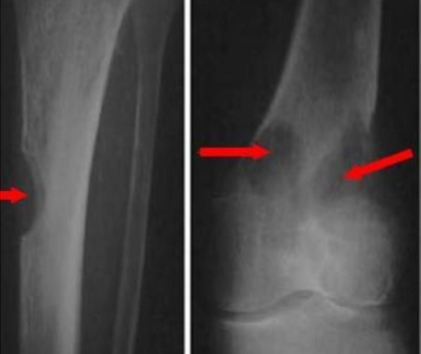

radiology - avascular necrosis

involves the bone with poor collateral blood supply such as the femoral head

most readily detected by MRI